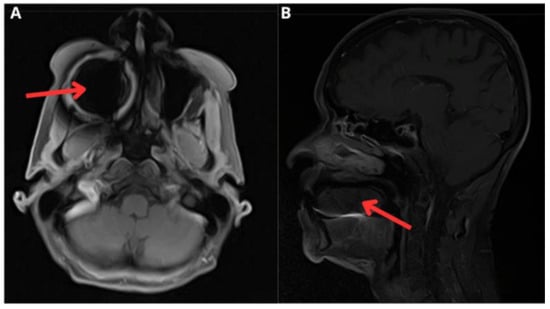

| Diagnostic aids | MRI of face and neck with contrast showing irregular enhancement measuring approximately 25 × 25 × 16 mm in pharyngeal mucosal space involving right palatine tonsil and base of tongue | PET CT * showing hypermetabolic nodule of right pharynx and palatoglossal arch measuring 22 × 10 mm | Endoscopy: moderate, active, non-atrophic chronic gastritis; no malignant neoplasia; Entero-MRI: distended stomach with compact image inside, nonspecific thickening of jejunal loops; contrast-enhanced abdominal CT |